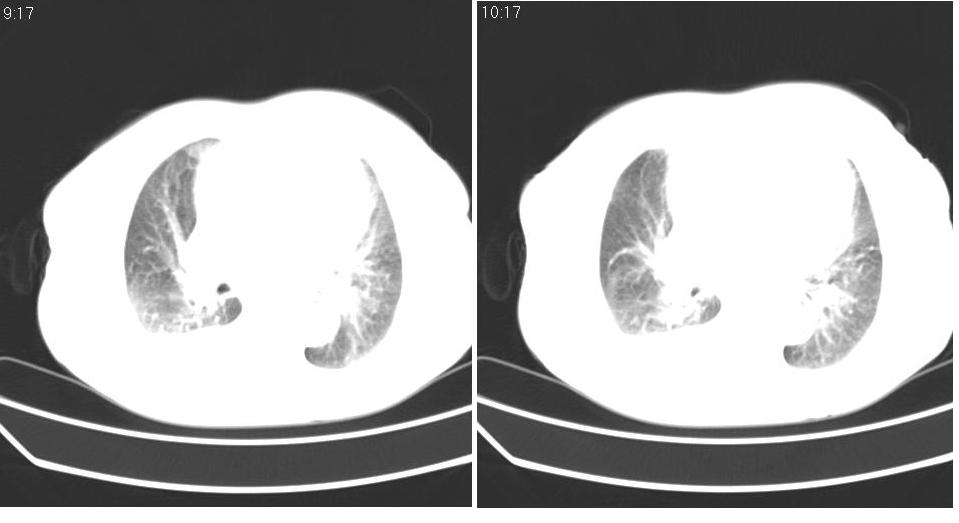

以下是引用liaizhi在2007-7-11 15:41:00的发言:[br]两肺纹理增粗,肺门影增大,气管支气管通畅。升主动脉壁及冠状动脉壁钙化。左房左室稍扩大。心包积液,胸腔积液。考虑冠心病并心功能不全,肺水肿,胸腔积液。

以下是引用zhangzhongshou在2007-7-11 13:16:00的发言:[br]1、冠状动脉钙化[br]2、心包积液[br]3、右侧胸腔积液[br]大家都考虑心衰,冠状动脉钙化、肺纹理增强,胸腔积液、心包积液,表面上是支持,但是为什么右侧有较多积液,左侧没有呢? 如果用结核性胸膜炎,并结核性心包炎也可解释,请楼主进一步提供临床资料。

以下是引用zrs在2007-7-11 14:40:00的发言:[br]支持心衰,心衰所至的胸腔积液常常是右侧多